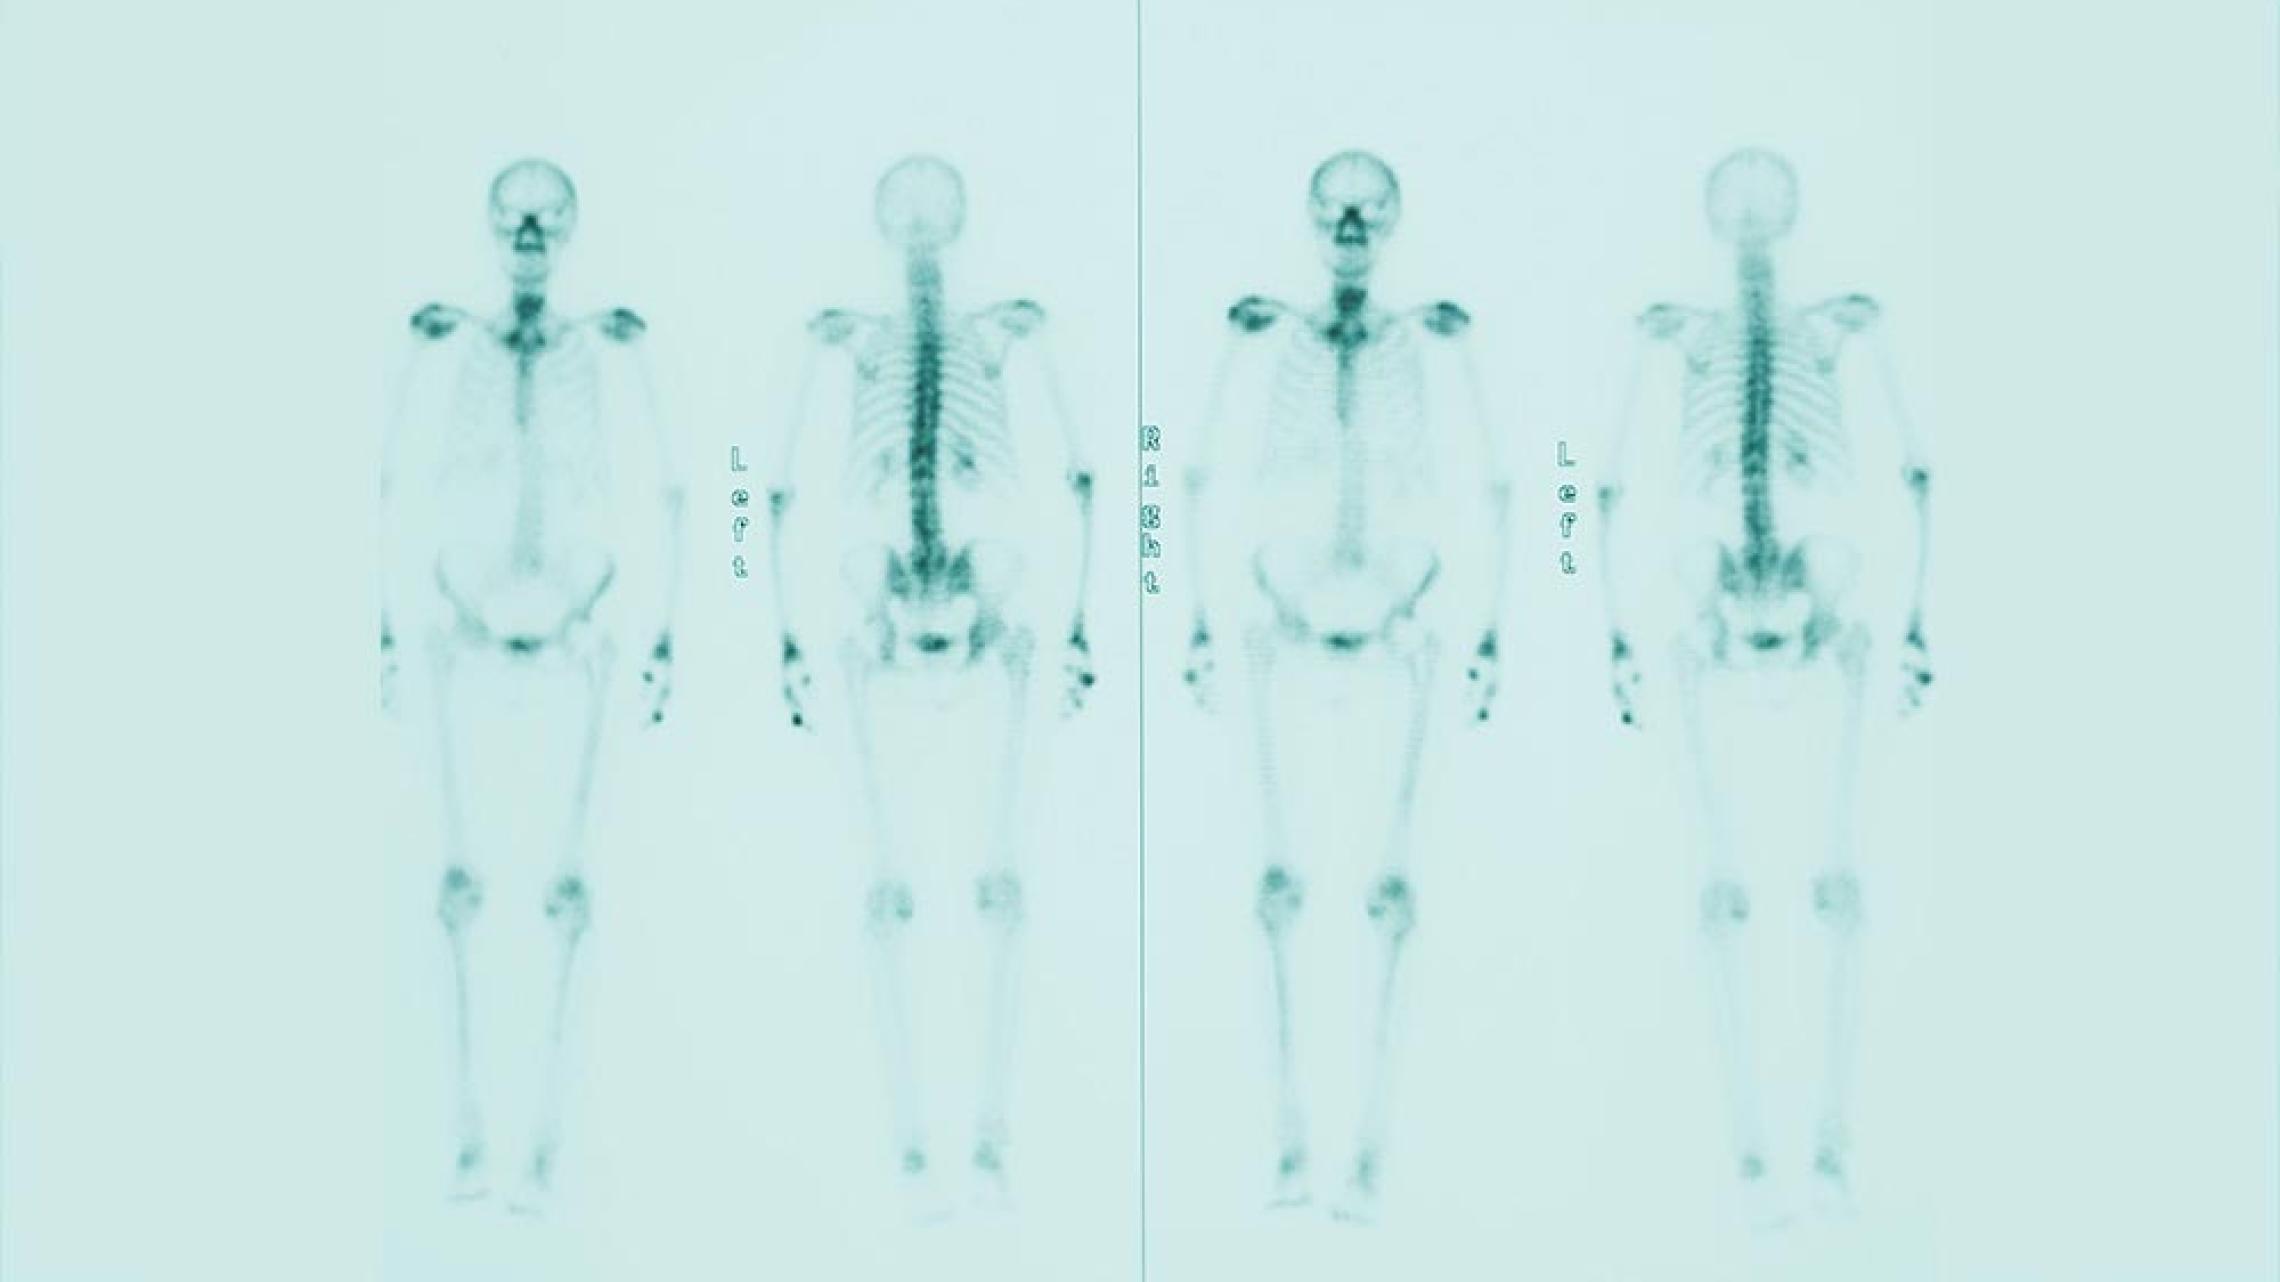

Szintigraphie

Die Szintigraphie ist ein nuklearmedizinsches Verfahren, bei der radioaktiv markierte Stoffe gespritzt werden.Deutsche Krebsgesellschaft (DKG) OnkoInternetportal Szintigrafie. https://www.krebsgesellschaft.de/onko-internetportal/basis-informationen-krebs/diagnosemethoden/szintigrafie.html Abgerufen am 11.06.24 Diese reichern sich in bestimmten Zielorganen besonders gut an und geben dort Strahlung ab.

Diese Strahlung wird mittels einer speziellen Kamera („Gammakamera”) erfasst und zu einem Bild („Szintigramm”) verrechnet.Deutsche Krebsgesellschaft (DKG) OnkoInternetportal Szintigrafie. https://www.krebsgesellschaft.de/onko-internetportal/basis-informationen-krebs/diagnosemethoden/szintigrafie.html Abgerufen am 11.06.24

Die Szintigraphie wird in der Onkologie vor allem zum Nachweis von Metastasen im Skelett eingesetzt (Skelettszintigraphie).Deutsche Krebsgesellschaft (DKG) OnkoInternetportal Szintigrafie. https://www.krebsgesellschaft.de/onko-internetportal/basis-informationen-krebs/diagnosemethoden/szintigrafie.html Abgerufen am 11.06.24

Zudem gibt es verschiedene weitere Indikationen für die Durchführung einer Szintigraphie, um gutartige Veränderungen von einem Tumor zu unterscheiden.Deutsche Krebsgesellschaft (DKG) OnkoInternetportal Szintigrafie. https://www.krebsgesellschaft.de/onko-internetportal/basis-informationen-krebs/diagnosemethoden/szintigrafie.html Abgerufen am 11.06.24

Die Strahlenbelastung bei der Szintigraphie ist gering; die radioaktiv markierten Substanzen werden innerhalb kurzer Zeit über Urin und Stuhl wieder ausgeschieden.Deutsche Krebsgesellschaft (DKG) OnkoInternetportal Szintigrafie. https://www.krebsgesellschaft.de/onko-internetportal/basis-informationen-krebs/diagnosemethoden/szintigrafie.html Abgerufen am 11.06.24